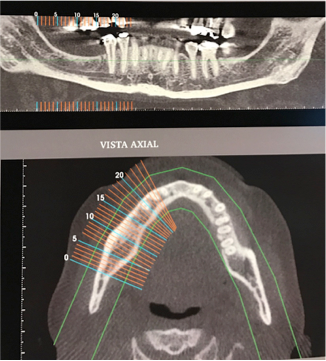

Paciente do sexo feminino, 52 anos, solicitou tratamento devido a aparência insatisfatória dos dentes, além da função mastigatória limitada. O tratamento foi iniciado na região posterior esquerda da mandíbula, a fim de garantir suporte para a futura reabilitação. O exame de tomografia computadorizada revelou altura óssea entre a crista e o canal mandibular insuficiente para colocação de implantes convencionais. Foi planejado a colocação de implantes na região vestibular do canal, com mínima distância do canal propriamente dito.

Fig. 1 e 2 Tomografia inicial